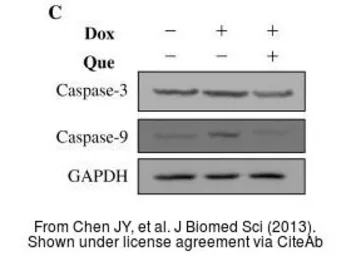

The data was published in the journal J Biomed Sci in 2014. PMID: 25200553

The data was published in the journal J Biomed Sci in 2014. PMID: 25200553

The data was published in the journal J Biomed Sci in 2014. PMID: 25200553

The data was published in the journal J Biomed Sci in 2013. PMID: 24359494

The data was published in the journal J Biomed Sci in 2013. PMID: 24359494